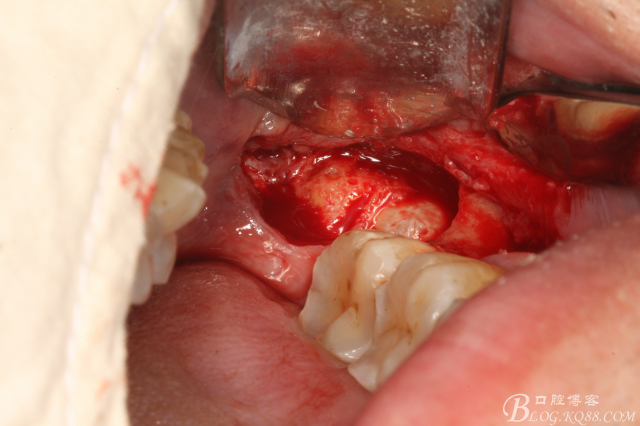

圖2.切開、翻瓣、去骨

圖三、完全暴露38牙根和牙冠